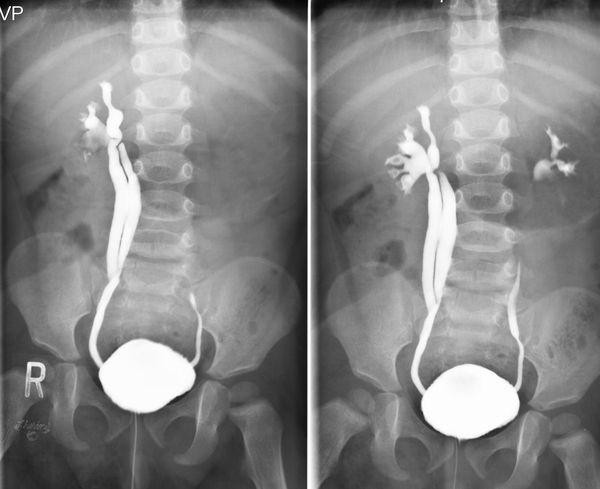

Кроме того, при повторяющихся инфекциях мочевыводящей системы ребенку также проводится углубленное обследование мочевыводящей системы. Золотой стандарт для точной диагностики рефлюкса — это микционная цистоуретрография1.

Во время данного исследования врач через катетер по мочеиспускательному каналу вводит рентгеноконтрастный препарат в мочевой пузырь. Затем выполняется два рентгеновских снимка:

1. Сразу после наполнения мочевого пузыря;

2. Непосредственно во время мочеиспускания.

Цистография позволяет обнаружить рефлюкс и определить его степень. На снимках при рефлюксе отчетливо видно, как контрастное вещество проникает в мочеточник и выше.

Кроме того, врачи используют единую классификацию ПМР, основанную на результатах микционной цистоуретрографии1. Согласно ей, урологи выделяют 5 степеней рефлюкса. Наиболее легкая первая степень. Для нее характерен заброс мочи только в мочеточник, без поражения почки. Наиболее тяжелая — пятая степень ПМР: выраженная деформация и извилистость мочеточника, расширение лоханок и чашечек, необратимые изменения в ткани почки.